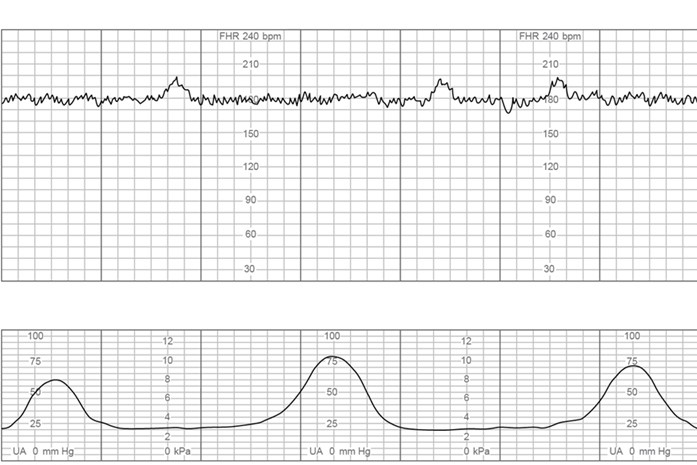

The charge nurse is observing fetal heart rate (FHR) tracings of 4 clients who have just been admitted to labor and delivery triage. Which FHR pattern would be most concerning to the nurse?

A)